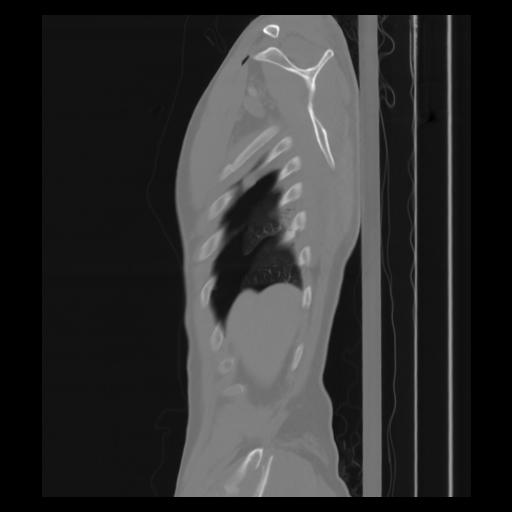

30 CUERPO,CE,Sagittal,3.000,CUERPO,Sagittal,